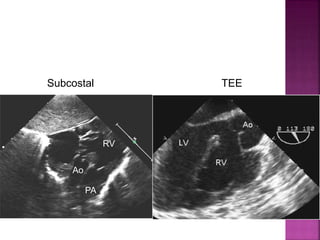

• subcostal coronal and sagittal planes; parasternal long axis

Guideline DORV

subaortic VSD

Subcostal TEE

Ao

RV

PA

subaortic VSD with severe subpulmonary obstruction